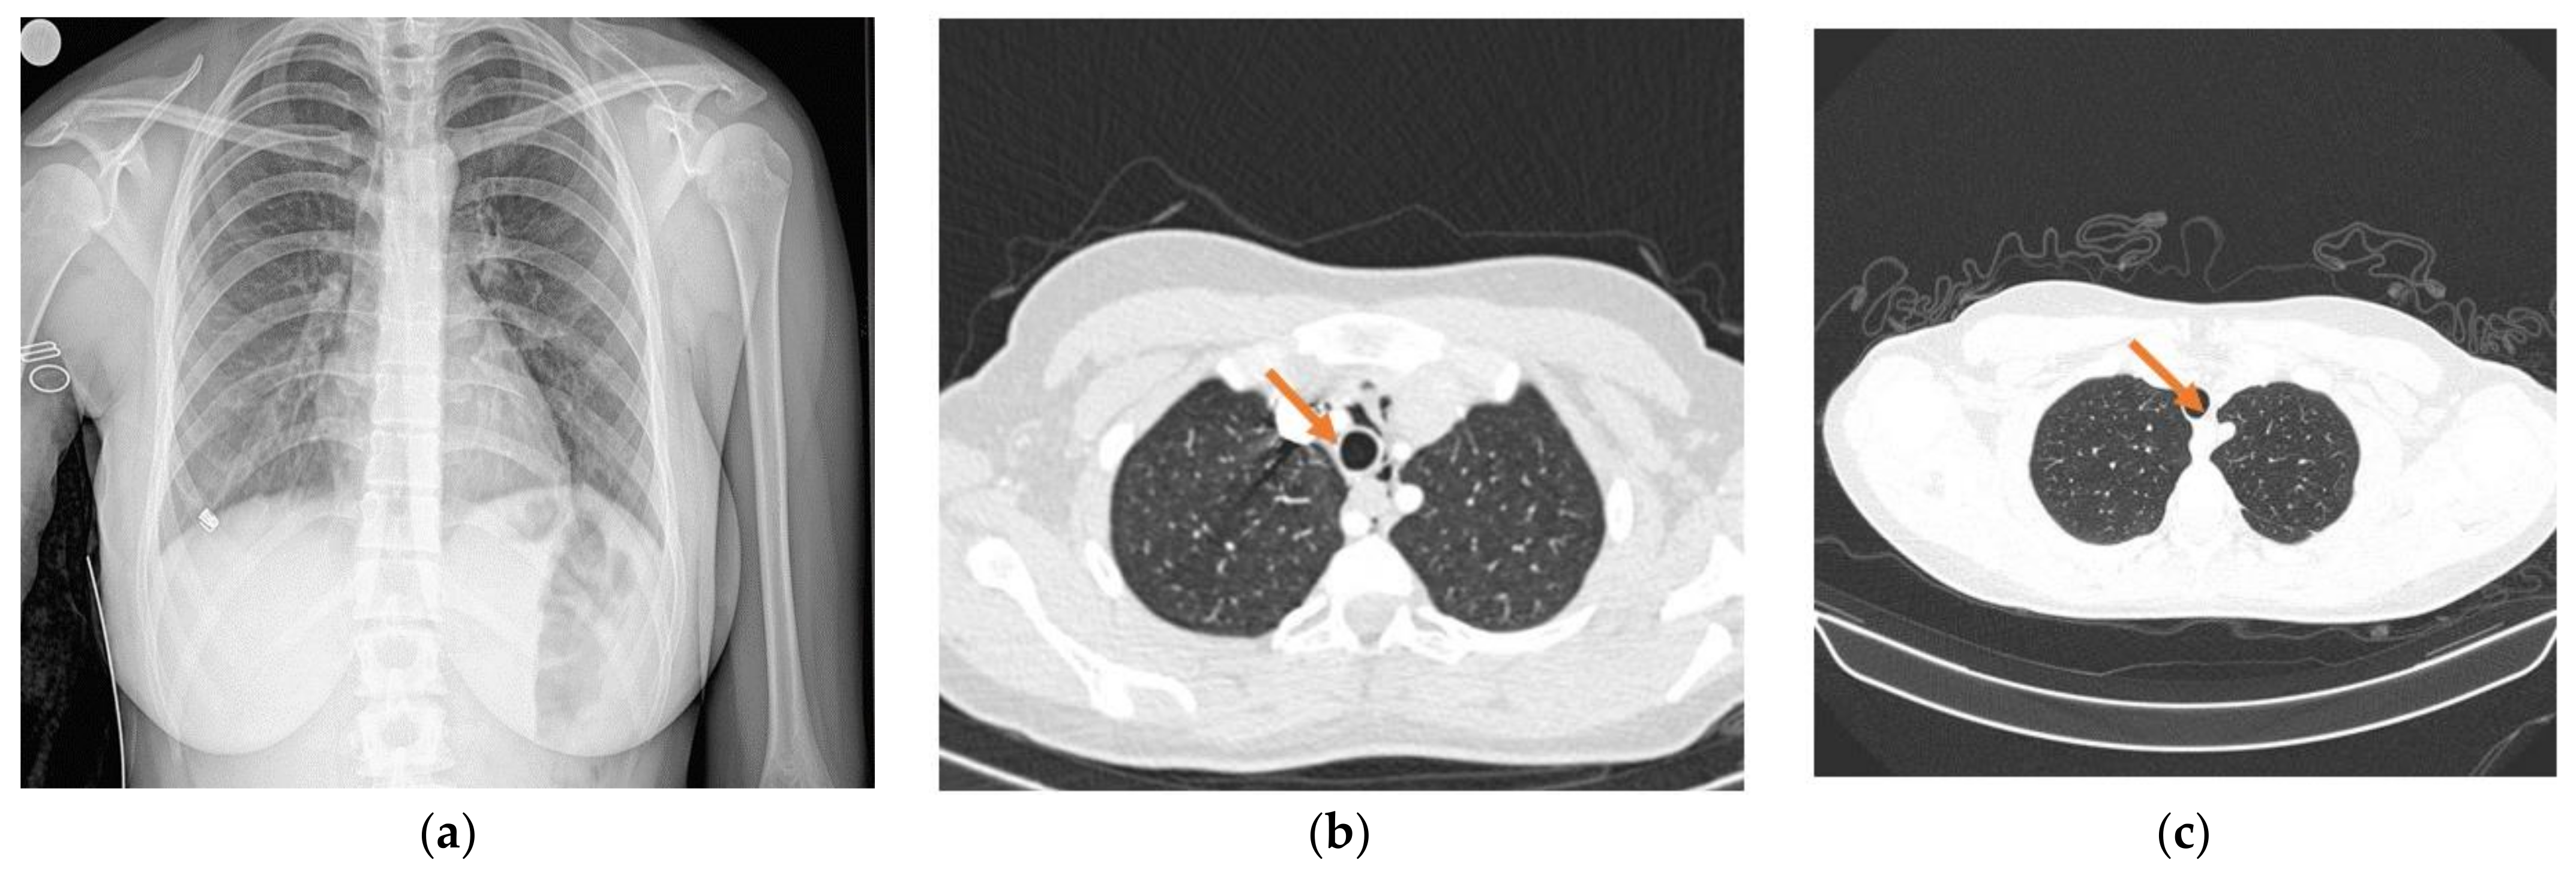

Spontaneous Pneumomediastinum in a 16-Year-Old Patient with SARS-CoV-2 Infection: A North-East Romanian Case

2. Case Report